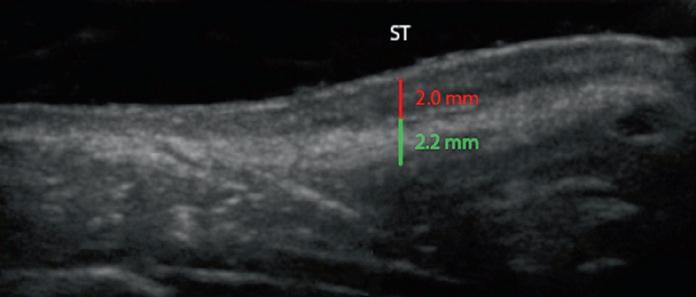

Fig. 1.21 Patient with a thick-skin STE composed of a thick lower part and thin upper part. (a, b) Preop sonogram and photo. (c , d) Views 4 weeks postop, prior to start of Accutane®. (e, f ) Views 4 months after surgery and 3 month course of Accutane. The vertical measurements show dermis (red ) and SMAS ( green). Note: there has been a full 1 mm thinning of the dermis (33%) and 0.6 mm of the deep soft tissue (25%). ST supratip; T tip

Patients who have a thick dermis benefit from preconditioning with a combination of salicylic acid, mechanical scrub, alpha hydroxyl acids, and retinoids to shrink the oil glands. Patients who have thick underlying soft tissue are routinely defatted using an open approach by dissecting at a subdermal level, followed by resection of the intervening soft tissues down to the cartilage level. Selected patients benefit from a postoperative treatment program with either 20 mg of isotretinoin (Accutane®) started at 4 weeks and continued for 4–5 months to decrease the size of the oil glands, with optional CO2 Fraxel® (Solta Medical; Hayward, CA) for textural smoothing. The patient shown in Fig. 1.21 had extremely thick skin, which was defatted intraoperatively. A dorsal graft was inserted to unify the two skin sleeves. sonogram